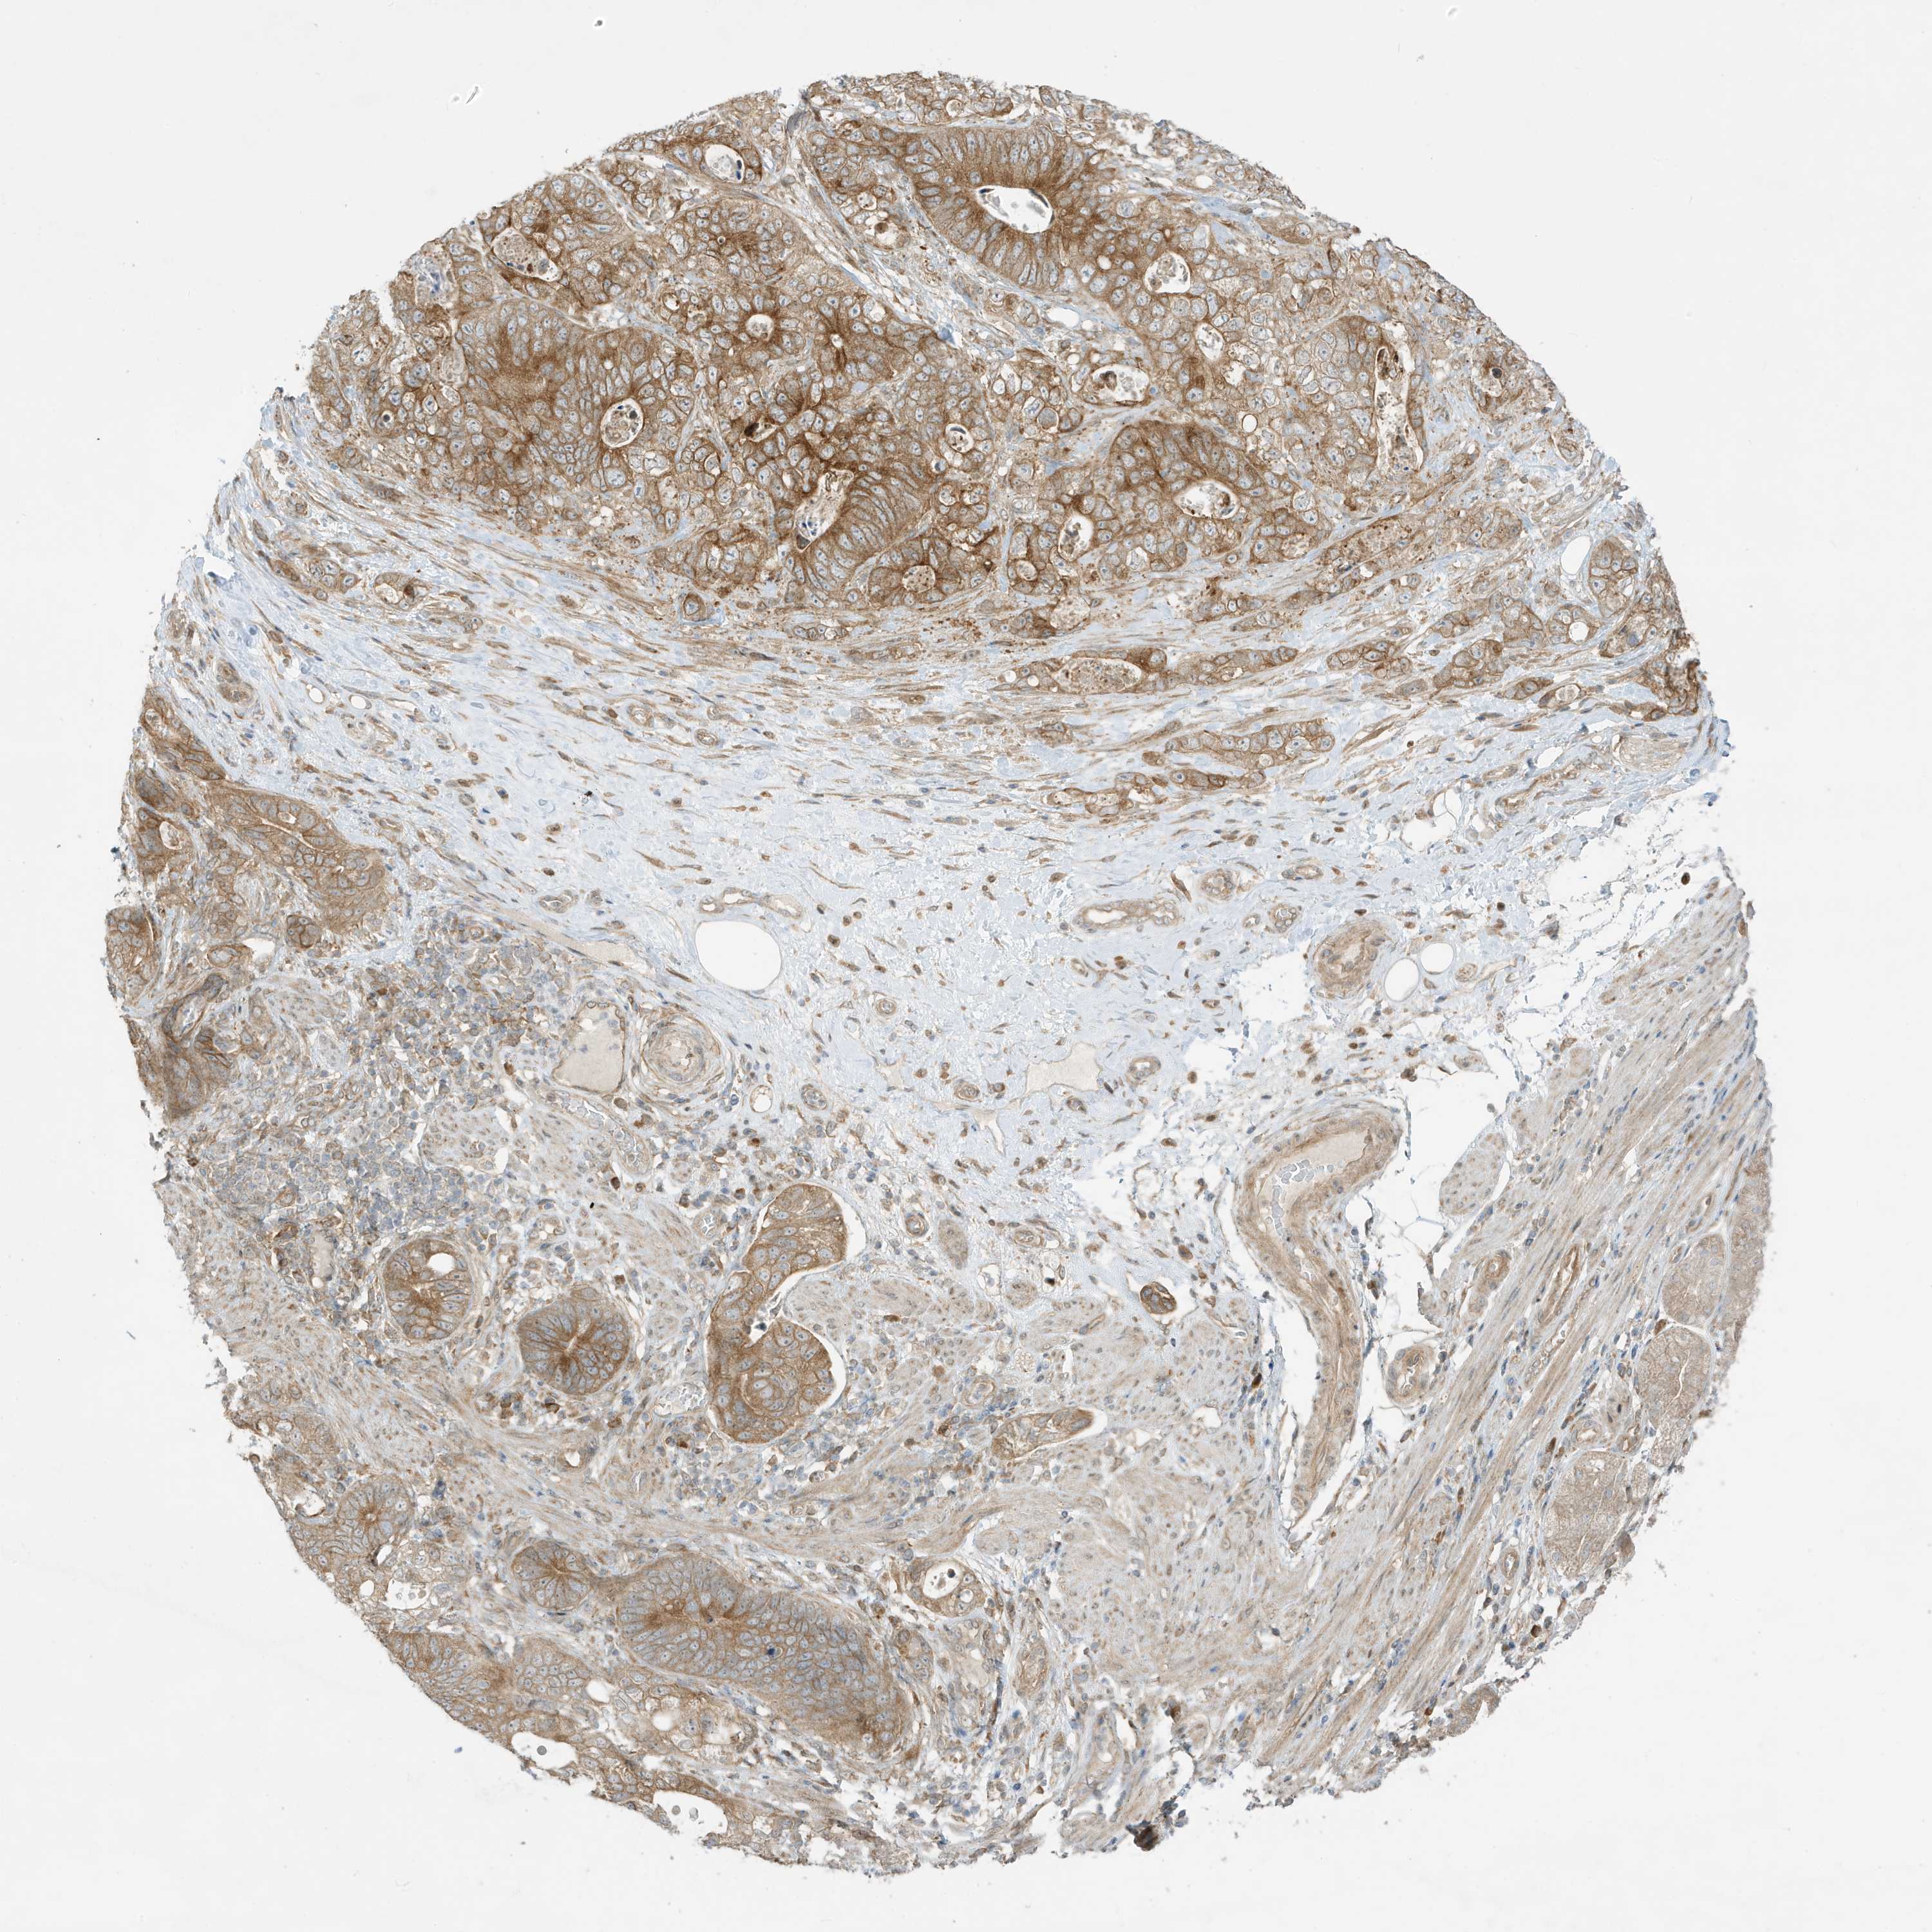

STOMACH CANCER - Protein expressioni

A mouse-over function shows sample information and annotation data. Click on an image to view it in a full screen mode. Samples can be filtered based on level of antibody staining by selecting one or several of the following categories: high, medium, low and not detected. The assay and annotation is described here.

Antibody stainingi

Antibody staining in the annotated cell types in the current human tissue is reported as not detected, low, medium, or high, based on conventional immunohistochemistry profiling in selected tissues. This score is based on the combination of the staining intensity and fraction of stained cells.

Each image is clickable and will lead to virtual microscopy that enables deeper exploration of all samples and also displays staining intensity scores, fraction scores and subcellular localization as well as patient and tissue information for each sample.

Antibody HPA035079

Staining

High

Medium

Low

Not detected

Intensity

Strong

Moderate

Weak

Negative

Quantity

>75%

75%-25%

<25%

None

Location

Nuclear

Cytoplasmic/membranous

Cytoplasmic/membranous,nuclear

Adenocarcinoma, NOS